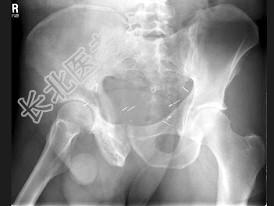

- 单项选择题男,56岁, 右髋部疼痛,5年前被确诊为前列腺癌, 结合图像,最可能的诊断是 ( )

A、骨纤维异常增殖症

B、转移性骨肿瘤

C、畸形性骨炎

D、内生软骨瘤

E、非骨化性纤维瘤